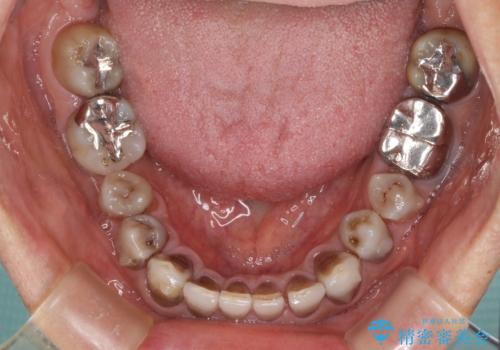

インビザラインは四六時中上下のマウスピースを介した咬合状態となるため、治療過程にて奥歯が接触しないという状態が続くことがあります。

奥歯の非接触は機能面において大きな障害であるため、この問題を解決しない限り矯正治療を終えることはできません。

インビザラインでの矯正治療が長期化してしまう要因の1つです。